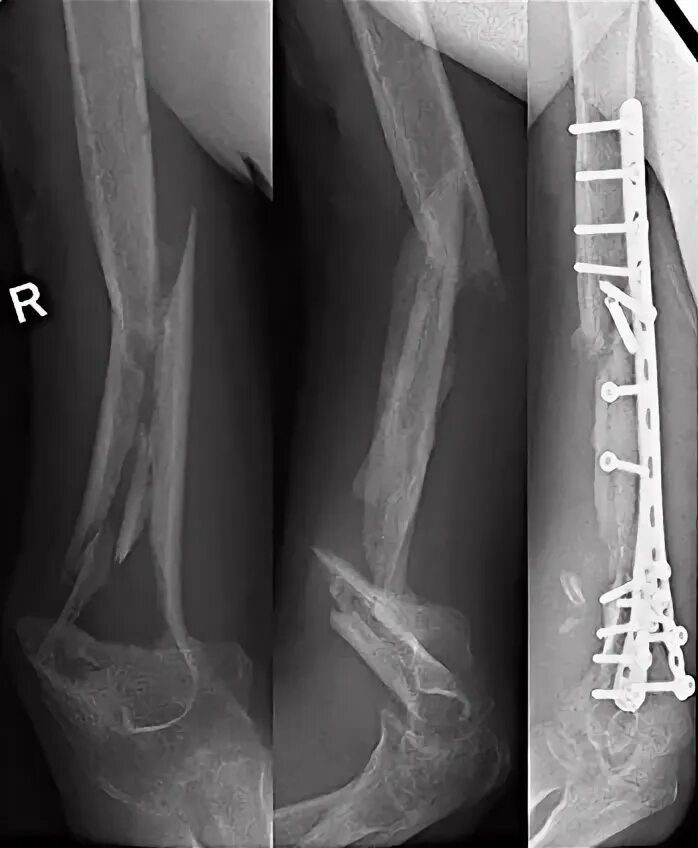

Оскольчатый перелом со смещением